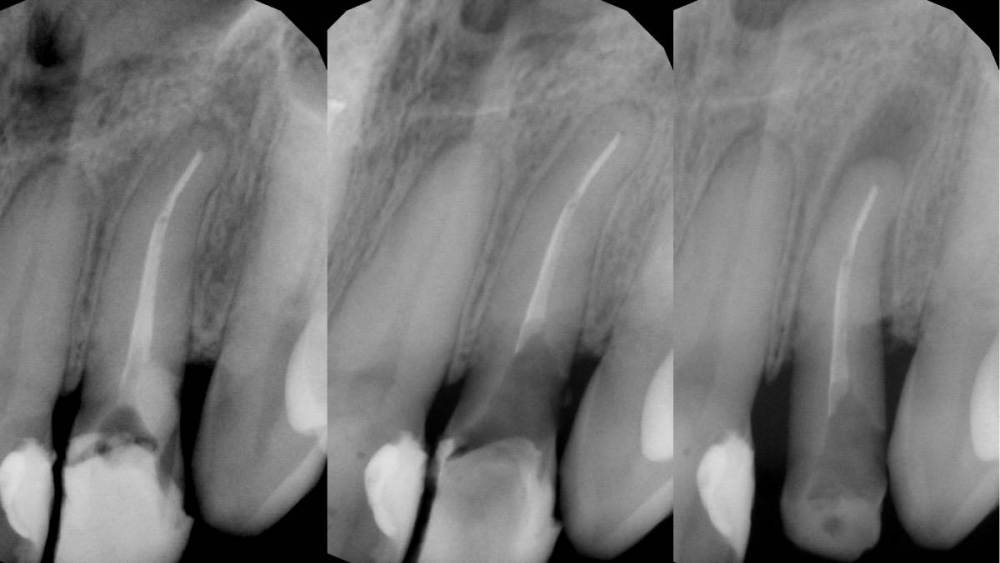

Гарриевич Опубликовано 21 марта, 2023 Автор Поделиться Опубликовано 21 марта, 2023 Пациент обратился с запросом обойти ступеньку и ложный ход в корневом канале образовавшиеся в ходе попытки перелечивания 2.2 зуба. Такде обнаружена глубокая поддесневая перфорация дистальной стенки закрытая композитом с признаками нарушения герметичности. Было решено произвести экструзию зуба 2.2 с последующим восстановлением коронкой. Экструзия производилась с помощью поперечно зафиксированного стекловолоконного штифта и ортодонтической цепочки. Из-за выраженной кривизны корня потребовалось 10 дней для достаточного вытяжения зуба. После вытяжения произведено эндодонтическое перелечивание и композитная надстройка культи. Зуб 2.2 зашинирован на 3 месяца. После периода ретенции ортопедом (Олег Саркисов) изготовлена провизорная коронка для формирования правильного десневого контура, которая через 3 недели была заменена на временную коронку длительного ношения. Через 4 месяца постоянная коронка из диоксида циркония зафиксирована на 2.2 зуб (также на 1.2/1.1/2.1). Осмотр через 1 год показывает хороший результат и сформировавшиеся десневые сосочки. Небольшой рубец пациента не беспокоит. Ортопед Олег Саркисов (bratok) Терапевт Юрий Кочаров 4 1 1 Ссылка на комментарий